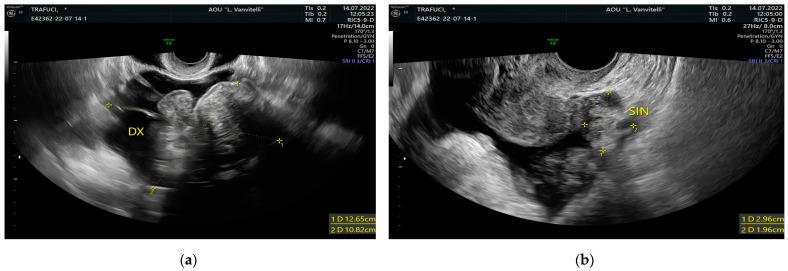

: Meigs syndrome is represented by a benign adnexal tumor, ascites, and hydrothorax. Even though the ovarian mass is often characterized by a fibroma-like origin, cancer antigen-125 (CA-125) serum levels could be elevated as in the development of ovarian cancer. Here, we present the case of a patient with Meigs syndrome and increased CA-125. : We performed systematic research for articles including similar cases in PubMed, EMBASE, and Scopus in February 2023, adopting the string of idioms: "Meigs syndrome AND Cancer antigen 125", and following the Preferred Reporting Items for Systematic Reviews and Meta-Analyses (PRISMA) statement. : Eligible records were 25. Hydrothorax was right-sided in 10 cases over 25; left-sided in two patients over 25. Concerning ascites, two patients showed more than 6 L of ascitic fluid, whereas three patients had 6 L or less. CA-125 elevation ranged from 149 IU/mL to 3803 IU/mL. Adnexal mass histotypes were: struma ovarii (12 cases), thecomas (two cases), fibrothecomas (five cases), fibromas (five cases), and one sclerosing stromal tumor (SST). : In postmenopausal women with elevated CA-125 serum levels and an adnexal mass suspicious for malignancy at ultrasound (US), ascites and pleural effusion, surgery, and histopathological examination are necessary. MS is a diagnostic option, with an excellent prognosis after exeresis of the mass.

梅格斯综合征的特征为良性附件肿瘤、腹水和胸腔积液。尽管卵巢肿块常表现为纤维瘤样起源,但癌抗原 125(CA-125)血清水平可能会升高,如同卵巢癌的发展过程一样。在此,我们报告了一例梅格斯综合征伴 CA-125 升高的患者。

符合条件的记录有 25 条。25 例中,10 例胸腔积液为右侧,2 例为左侧。关于腹水,2 例患者的腹水量超过 6 L,3 例患者的腹水量为 6 L 或更少。CA-125 升高范围为 149 IU/mL 至 3803 IU/mL。附件肿块组织学类型为:卵巢甲状腺肿(12 例)、卵泡膜细胞瘤(2 例)、纤维卵泡膜细胞瘤(5 例)、纤维瘤(5 例)和 1 例硬化性间质瘤(SST)。

对于绝经后妇女,若血清 CA-125 水平升高且超声(US)检查怀疑附件肿块恶性、腹水和胸腔积液,手术和组织病理学检查是必要的。MS 是一种诊断选择,切除肿块后预后良好。